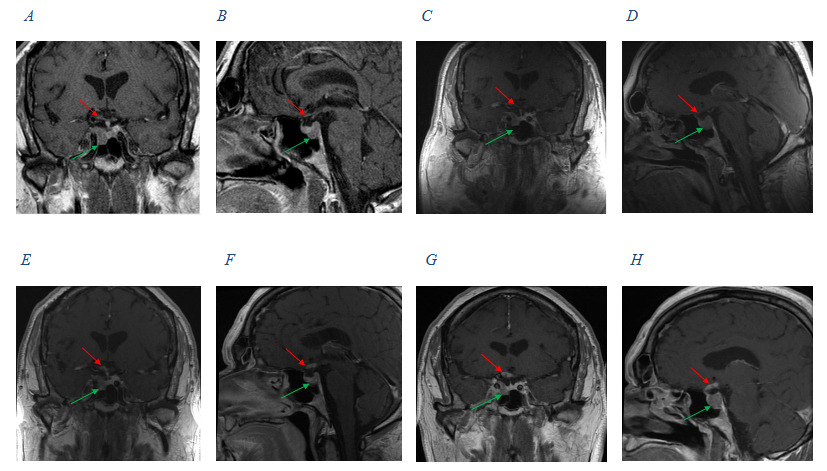

At that eye examination (now 2 years after radiotherapy), preliminary testing and anterior and posterior ocular evaluations were normal. There was also no visual field loss (Figure 2). Ten weeks later, the patient returned with right vision loss followed by vision loss in his left eye, which started 8 weeks prior. Visual acuity was no light perception in the right eye and 20/60 in the left eye. Preliminary tests confirmed an afferent pupillary defect in the right eye, and posterior pole findings revealed pallid nerves in both eyes (Figure 4). OCT retinal nerve fiber layer measurements revealed significant thinning compared with baseline (Figure 4). The 30-2 Humphrey visual fields revealed a new complete junctional scotoma (Figure 5). He denied any headache, nausea, diplopia, jaw claudication, weight loss, or fatigue symptoms. The patient was referred for urgent magnetic resonance imaging of the orbits, chiasm, and brain, and neurosurgery was paged. Initial imaging revealed no change to the macroadenoma from prior studies following his radiation treatment and no mass effect of the remaining tumor on the optic chiasm (Figure 3). The initial radiology interpretation indicated that there was no contrast enhancement of the visual pathway on T1 images. This excluded the differential diagnoses of macroadenoma regrowth, pituitary apoplexy, or other compressive lesions of the optic chiasm or optic nerves. Insulin-like growth factor-1 and growth hormone levels were normal. This prompted an evaluation for new onset optic nerve atrophy. Giant cell arteritis was excluded by blood work, including a complete blood count, erythrocyte sedimentation rate, C-reactive protein, as well as a temporal artery biopsy. All were normal. Further laboratory tests included Syphilis immunoglobulin G, Lyme serology, antinuclear antibody, vitamin B12, folate, QuantiFERON, and angiotensin converting enzyme. A computed tomography scan of the lungs was also ordered, as well as a lumbar puncture. Cerebral spinal fluid analysis was normal to include cell count, glucose, chloride, glutamine, lactate dehydrogenase, opening pressure, aquaporin-4 immunoglobulin G, and VDRL test. There were no myelin basic proteins found, no oligoclonal bands, and no cancerous, fungal, or bacterial cells present. All additional tests returned normal and without suspected pathology. At this time, the diagnosis was presumed radiation-induced optic neuropathy and neurosurgery ordered a series of 4 repeat contrast-enhanced magnetic resonance imaging over the following 3 weeks to evaluate for any potential macroadenoma growth, which all returned without a change in mass (Figure 3). However, there was abnormal enhancement on contrast-enhanced T1 images that began initially on the right optic nerve and subsequently spread to the optic chiasm and to both optic tracts (Figure 3), confirming posterior radiation-induced optic neuropathy. Of note, even though the initial imaging report (after the onset of visual symptoms) indicated that there was no enhancement along the visual pathway, a meeting with a multispecialty board years after his diagnosis did verify subtle enhancement in the right optic nerve near the chiasm in imaging immediately following his vision loss (Figure 3).

At this point, it was concluded that the patient likely had posterior radiation necrosis of the optic nerve and chiasm, despite receiving safe radiation levels. Approximately 3 weeks after his visual symptoms began, repeat magnetic resonance imaging confirmed the diagnosis of radiation-induced optic neuropathy, as his T1 contrast-enhanced images revealed an abnormal enhancement along the right optic nerve, optic chiasm, and both optic tracts. A review of this case with a multispecialty board years after his diagnosis, indicated that subtle enhancement of the right optic nerve was also present during his first imaging following his vision loss. Hudgins et al recommends all patients with suspected posterior radiation optic neuropathy receive gadolinium-enhanced, fat-suppressed T1 weighted images of the optic nerve and chiasm, as unenhanced T1 and T2 images will look unremarkable.14 This nonspecific enhancement can be found along the affected segment, but it is often difficult to capture and therefore cannot be relied on to make a diagnosis of posterior radiation-induced optic neuropathy.8 Such enhancement may present from 2 to 17 months after the initial vision loss and can be transient.8 In addition, the technique needed to visualize this change is specific, as lack of fat suppression or saturation techniques can cause this enhancement to not be visualized.14 This case highlights how difficult it can be to visualize this enhancement, thus leading to a difficult or delayed confirmed diagnosis of radiation-induced optic neuropathy.